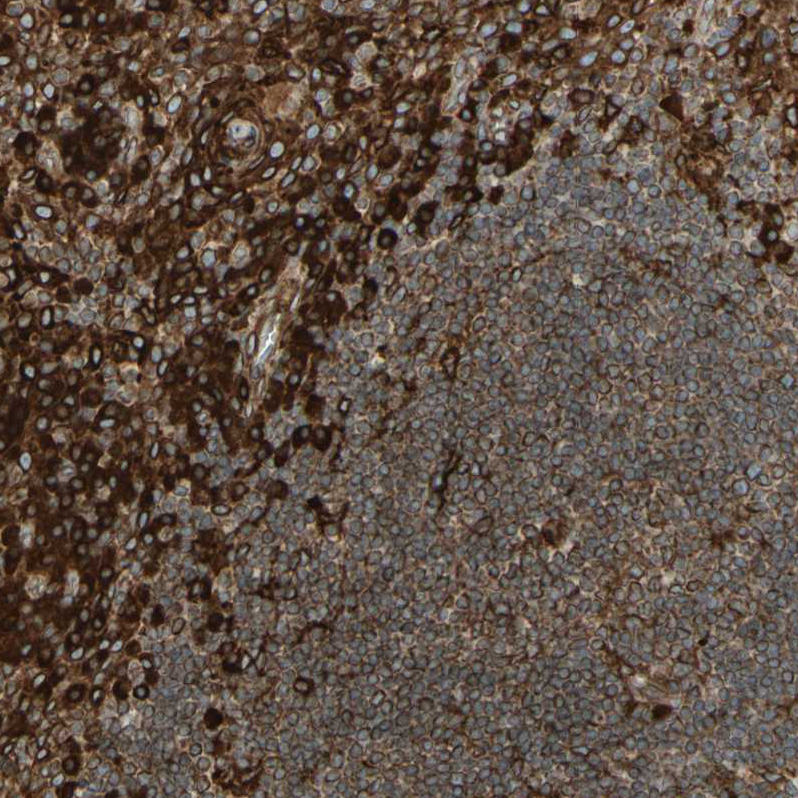

Immunohistochemical staining of human cerebral cortex, placenta, testis and tonsil using Anti-CANX antibody HPA009433 (A) shows similar protein distribution across tissues to independent antibody HPA009696 (B).